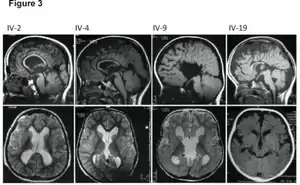

| MRI images showing megalencephaly in four family members who all have unusually large skulls (the family is affected by an autosomal recessive syndrome caused by a KIF7 mutation that induces multiple epiphyseal dysplasia)[1] | |